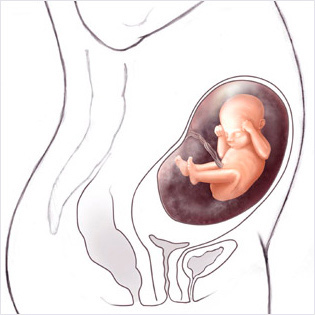

Bu haftadan itibaren artık bebek rahim içerisinde oldukça fazla yer kaplar ve bu yüzden ona hareket edecek fazla alan kalmaz. Eğer bebeğinizin hareketlerinde azalma his ederseniz endişe etmeyin, hareketlerin azalması bu yüzdendir.

Bebeğin Boyutu: 43.7 cm, 1.9 kg

Hamileliğin (Gebeliğin) 35. Haftası Resim ve Video;